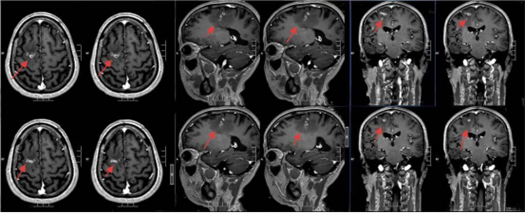

该院神经外二科张旭标副主任医师接诊后,根据影像结果,发现其右额叶病变,局部肉芽肿形成伴周围组织水肿。

“这是大脑为了隔离‘入侵者’筑起的一道‘隔离墙’,周围的脑组织被刺激得肿胀。”张旭标解释,这些影像特征高度指向脑裂头蚴病。经比对,病灶范围稳定,手术时机成熟。

术前影像

手术采用神经导航技术,精确定位病变,张旭标在显微镜下小心抓取寄生虫、清理“虫窝”,避免损伤周围功能区脑组织。一条长约10厘米的灰白色寄生虫被完整取出。术后病理报告证实为裂头蚴。